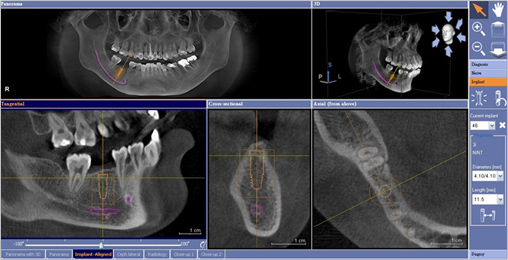

CT對於植牙手術,最大的便利性之一,即是具有模擬各家廠牌植體的功能,讓牙醫師在術前判斷植體埋入的位置是否恰當。由於CT所拍攝出來的影像是立體的,可以360度旋轉,進一步判斷植體的寬度,避免因為患者的顎骨結構的不同,穿到顎骨的外側,或是壓迫到神經。

CT能做植體與牙齒的360度檢查,並模擬植體,安效提高手術安全性

電腦模擬植牙示意圖